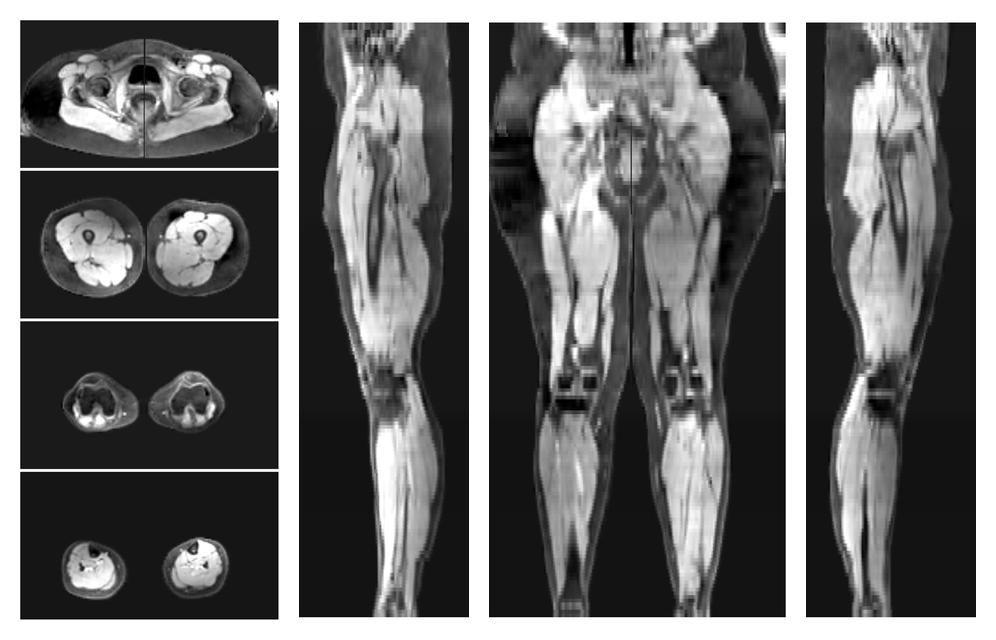

• Water only signal

The water part of the acquired multi-echo spin echo data.